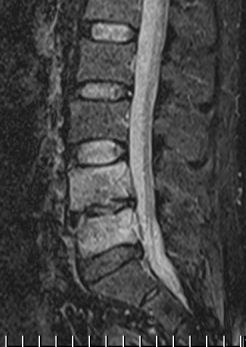

В динамике общий анализ крови гемоглобин - 140 г/л; эритроциты - 4,0 × 10 12 ; цветной показатель - 0,9; лейкоциты - 5,6× 10 9 ; СОЭ-15 мм/ч, остальные анализа без особенностей. На МРТ в динамике через 3 недели инфильтрация уменьшилась, но сохраняется, патологический сигнал от тел VL4-5 сохраняется. Клинически резка боль при движении в поясничном отделе позвоночника с распространением болей в нижние конечности, нестабильность позвоночника.

Рис. 3. МРТ после 20 дней терапии Левофлоксацином